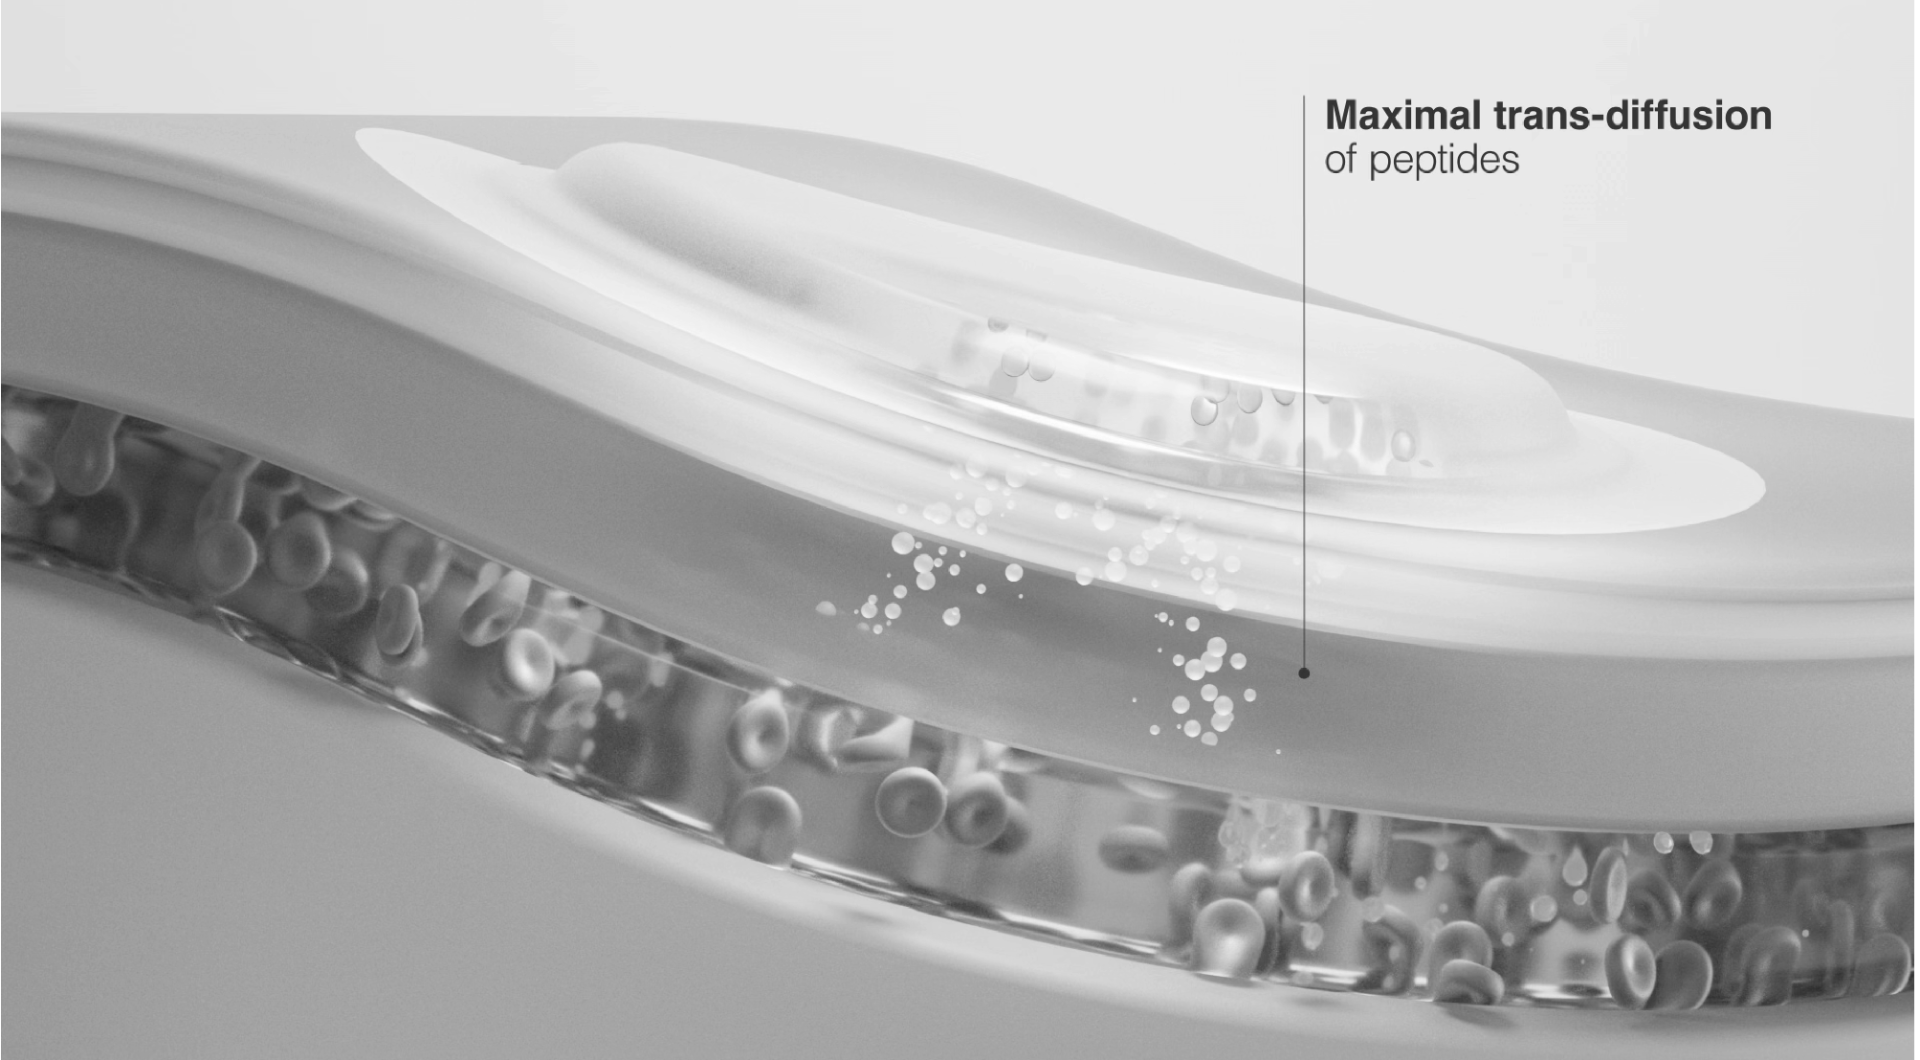

TD-IntelGel™ Coupled with Muco-SmartSeal®

Stabilized Matrix Delivery

Peptides are embedded in a stabilized hydrogel matrix enabling controlled trans-diffusion through buccal membrane with consistent release and enhanced systemic absorption efficiency

SmartSeal Barrier

Muco-SmartSeal® technology creates a secure peripheral seal preventing peptide leakage into saliva and minimizing washout into gastrointestinal tract for targeted absorption